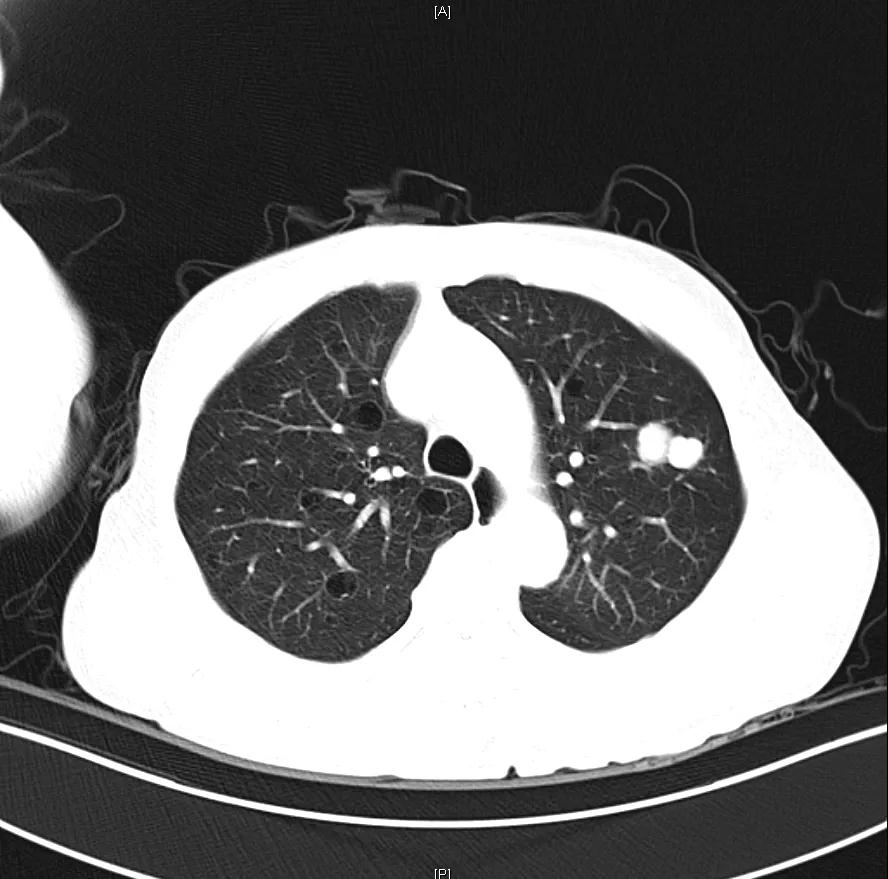

肝脏弹性超声:12kPa。腹部MRI平扫+增强:肝巨块结节性HCC(最大径18.4cm)伴肝内多发转移(最大径3.5cm),肝右静脉广泛癌栓形成;肝硬化伴门脉高压、脾大、少量腹水;肝囊肿;双肺多发转移。胸部CT平扫:两肺多发转移,两肺气肿伴肺大泡,两肺散在慢性炎症,右侧少量胸水。

Δ肺CT:双肺多发转移